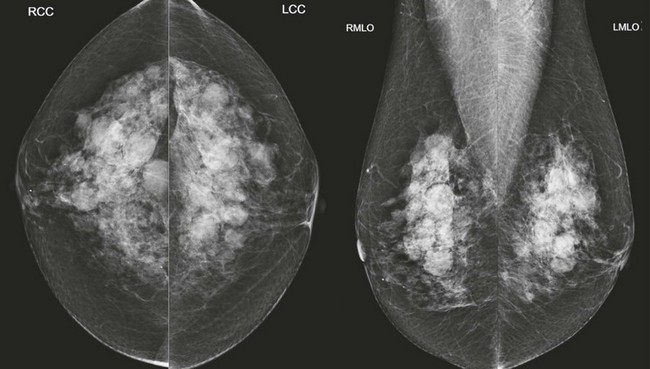

FIGURE 8-6 Multiple Masses with Malignancy.

Screening mammogram of a 40-year-old woman (A). Multiple masses are seen bilaterally (arrows). A right breast mass is dense for its size (open arrow). The patient was recalled and this mass is shown to have spiculated margins on a craniocaudal (CC) spot compression view (open arrow; B, top). US shows a corresponding hypoechoic solid mass with indistinct margins (B, bottom). Two left breast cysts were also seen. Diagnosis: IDC and ductal carcinoma in situ (DCIS) in the right breast.